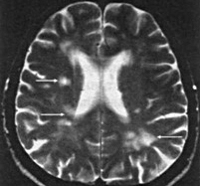

Термин « инфаркт мозга» приобретает все большее распространение с широким применением методов нейровизуализации, позволяющих уточнить локализацию и размеры ишемического очага и предположить его природу. Однако по своему смыслу термин «инфаркт мозга» не вполне эквивалентен термину «ишемический инсульт».

Ишемический инсульт – клиническое выражение инфаркта мозга, а инфаркт мозга – морфологический субстрат ишемического инсульта.

— КТ и/или МРТ-ангиография;